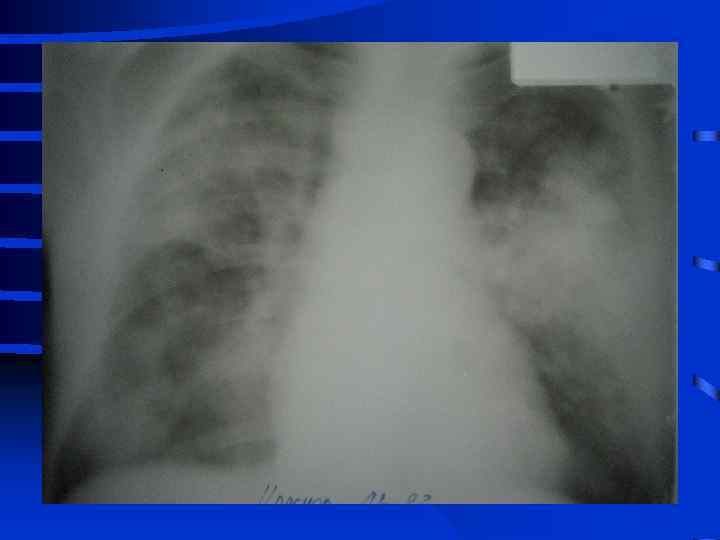

• I стадия Все изменения носят умеренный характер, индекс оксигенации (Pa. O 2/Fi. O 2) более 300, Pa. CO 2 снижен до 34 - 32 мм. рт. ст. , рентгенографически полнокровие легких, ячеистая деформация на фоне усиленного легочного рисунка. • II стадия Повторное, часто резкое ухудшение состояния. Психические нарушения (беспокойство, неадекватность), тахикардия свыше 110 - 120 в мин. , АД сист. более 150 мм. рт. ст. , индекс оксигенации менее 250 - 200, артериальная гипокапния. Рентгенографически - появление мелкоочаговых теней на периферии

• III стадия необходима респираторная поддержка, сознание нарушено, индекс оксигенации менее 200, шунтирование 30 - 50% от величины МОК. Появляются признаки полиорганного поражения: нарушение функции кишечника (парезы, острые язвы) • и почек (эпизоды олигурии) • Рентгенографически - сливные тени, иногда первые признаки гидроторакса

• IV стадия появляются симптомы присоединения инфекции с развитием гнойного трахеобронхита и пневмонии (госпитальной), признаки сепсиса, вторая волна полиорганной недостаточности. Индекс оксигенации менее 100, появляется гиперкапния. Рентгенографически - резкое снижение прозрачности легочных полей, множественные хлопьевидные тени (“снежная буря”).

Объективные признаки развития ОРДС • 1. Индекс оксигенации снижен • 2. Симметричные рентгенографические изменения инфильтративного характера • 3. Увеличение внутрилегочного шунта (более 25% от величины МОК) • 4. Возрастание альвеолярно-артериальной разницы по кислороду (более 250 мм. рт. ст. при Fi. O 2 = 1, 0) • 5. Легочная гипотензия (PCWP не более 12 мм. рт. ст. ) • 6. Уменьшение растяжимости (податливости) легких 50 мл/см. вод. ст. и менее

Тяжесть ОРДС по J. Murray (1988) • А) Рентгенография (инфильтрация от 0 до 4 квадрантов = 0 - 4 балла • Б) Гипоксия (PAO 2/Fi. O 2) от 300 и выше до 100 и менее = 0 - 4 балла • В) Растяжимость легких (от 80 и более до 20 и менее мл/см. вод. ст. ) = 0 - 4 балла • Г) ПДКВ при ИВЛ (от 0 до 14 см. вод. ст. и выше) = 0 - 4 балла • К от 0, 1 до 2, 5 - умеренное повреждение, более 2, 5 - тяжелое